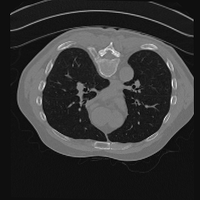

Exp. 3: Adult thorax data: To show the versatility of our approach we also apply it to adult thorax scans. For this experiment no organ specific training is performed but the whole volume is used. We evaluate reconstruction performance similar to Exp. 1 and Ti^^subscript𝑇𝑖\hat{T_{i}} prediction performance when ΩΩ\Omega is projected on an external plane, comparable to X-Ray examination using C-Arms. The latter provides insights about our method’s performance when applied to interventional settings in contrast to motion compensation problems. 60 healthy adult thorax scans were randomly selected, 51 scans used for ΩtrainsubscriptΩ𝑡𝑟𝑎𝑖𝑛\Omega_{train} and nine scans used for ΩvalidationsubscriptΩ𝑣𝑎𝑙𝑖𝑑𝑎𝑡𝑖𝑜𝑛\Omega_{validation}. Each scan is intensity normalised and resampled in a volume of 200×200×200200200200200\times 200\times 200 with spacing 1mm×1mm×1mm1𝑚𝑚1𝑚𝑚1𝑚𝑚1mm\times 1mm\times 1mm. Using the Fibonacci sampling method, 25 sampling plane of size 200×200200200200\times 200, evenly spaced between -50 and +50, were rotated over 500 normals. Training took approximately 20 hours for 60 epochs. Fig. 4c shows an example reconstruction result gaining 28dB PSNR with additional SVR. Ti^^subscript𝑇𝑖\hat{T_{i}} prediction takes approx. 20 ms/slice for this data.

Figure 4: (a): Comparison of a single slice from raw low-dose thorax CT data; (b): reconstruction based on SVRNet Ti^^subscript𝑇𝑖\hat{T_{i}} regression; (c): SVR initialized with SVRNet transformations after four iterations of SVR; (d): PSNR of (b) and (c) compared to (a). (e): shows a projection of an unseen pathological test CT volume as DRR and (e) shows a DRR at the location predicted by our method when presented with the image data in (e).

We use Siddon-Jacobs ray tracing [15] to generate Digitally Reconstructed Radiographs (DRRs) from the above described data. For training, we equally sample DRRs on equidistant half-spheres around 51 CT volumes at distances of 80cm, 60cm, and 40cm, between 90superscript90-90^{\circ} and 90superscript9090^{\circ} around all three co-ordinate axes. For validation, we generate 1000 DRRs with random rotation parameters within the bounds of the training data at 60cm distance from the volumetric iso-centre. We trained on healthy volunteer data and tested on nine healthy and ten randomly selected pathological volumes (eight lung cancer and two spinal pathologies). Our approach is able to predict DRR transformations relative to the trained reference co-ordinate system with an average translation error of 106mm and 5.6superscript5.65.6^{\circ} plane rotation for healthy patients, and 130mm and 7.0superscript7.07.0^{\circ} average error for pathological patients. An example is shown in Fig. 4e,f. Note that these values are good enough to robustly initialize intensity-based registration refinement. SVRNet prediction can be improved by generating a denser training data set, in particular, in more equidistant half-spheres.